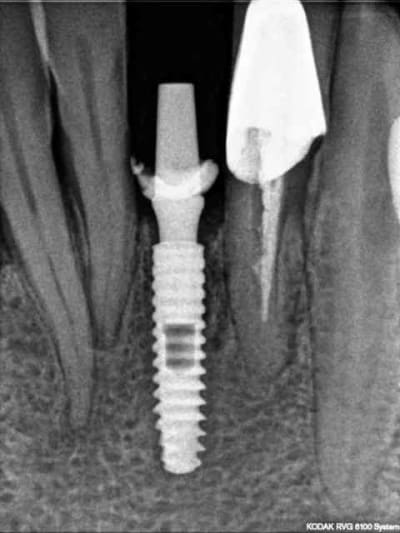

8) radio (faut dire que le couloir dans lequel on peut mettre l'implant est étroit)

1) j+8 jours

2) radio de contrôle